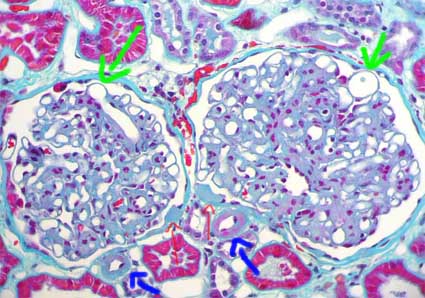

Otras dos lesiones glomerulares, llamadas exudativas (al igual que la hialinosis arteriolar), son la gota capsular y la hialinosis glomerular. La primera es un depósito homogéneo, hialino, en la cápsula de Bowman, suele ser redondeado o elongado y es altamente sugerente de ND, aunque no patognomónico (puede verse muy ocasionalmente en hipertensión y otras lesiones glomerulares nodulares idiopáticas). La hialinosis glomerular resulta de la extravasación de componentes plasmáticos que se acumulan en segmentos periféricos del penacho capilar, es también llamada gorro hialino o gorro de fibrina ("hyalin cap" o "fibrin cap") (Figuras 6, 7 y 8). En muchos casos con lesions típicas se evidencian microaneurismas producidos por mesangiolisis (Figuras 8 y 9).

Figura 8. En esta imagen podemos ver cuatro alteraciones de la ND: ensanchamiento mesangial por expansión de la matriz; hialinosis arteriolar, en este caso nodular (flechas azules); dos gotas capsulares, una en cada glomérulo (flechas rojas, delgadas); y microaneurismas (flechas verdes), lesiones frecuentes en ND que se suelen asociar a áreas focales de mesangiolisis. (Tricrómico de Masson, X400).

En vasos suele haber lesiones notorias; el cambio más característico es el engrosamiento hialino intimal de arteriolas, a veces nodular (Figuras 8 y 9). Si es muy prominente debe alertarnos sobre la posibilidad de ND sobre todo en jóvenes. Las lesiones arteriolares pueden comprometer cualquier arteriola; si evidenciamos en un glomérulo determinado hialinosis en la arteriola aferente y en la eferente es virtualmente patognomónico de ND. En arterias hay fibrosis intimal (arterioesclerosis), pero no se diferencia de la que se produce en otras enfermedades.